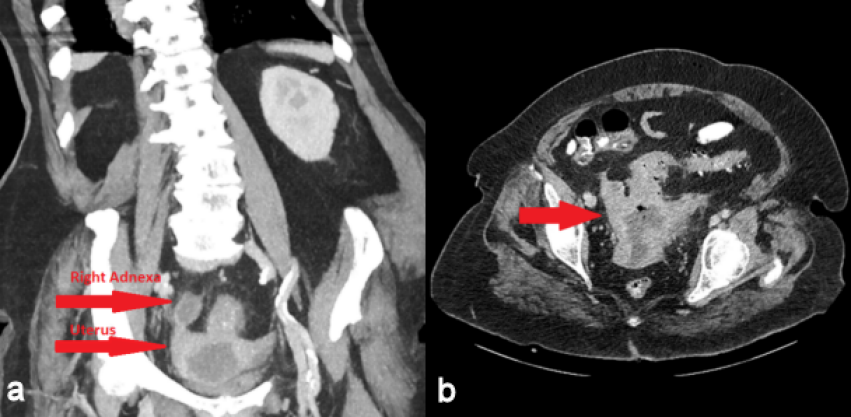

A 72-year-old woman was admitted to our emergency department with intermittent abdominal pain, diarrhea and fever up to 38.5°C for the last three days. The patient had a history of hypertension, dyslipidemia and alcoholism. She had one vaginal delivery in the past while her gynecological history was unremarkable. Her blood pressure was 100/70 mmHg, her pulse rate was 110 beats/min and her body temperature 38°C. The physical examination revealed mild sensitivity in palpation of the lower abdomen. Laboratory studies on her admission showed a white blood cell count of 25,000/µL (normal range 4–11x103/µl) with 79.3% neutrophilia (normal range 40–75%), crp 56 mg/dl (normal value <0.5) and creatinine 5.45 mg/dl (normal range 0.6–1.1 mg/dl) due to sepsis. Blood and urine culture was collected. Chest X-ray was normal. Ceftriaxone 2 gr twice daily and metronidazole 500 mg three times daily were administered promptly. The patient was observed in a high dependency unit for the first 3 days of hospitalization, but she was not intubated. The third day of her hospitalization, increased noisome vaginal discharge was observed and a gynecological assessment was requested. The optical examination of the cervix showed a purulent outflow through the cervical canal, and a pus culture was done. The pelvic exam revealed severe sensitivity in the lower pelvis. The transvaginal ultrasound examination showed an enlarged, integral uterus without any signs of perforation, hypoechoic fluid accumulation in the uterine cavity, unclear borders between endometrium – myometrium (Figure 1a [Fig. 1]), a mixed echogenic mass with a long axis of 38 mm in anatomical position of the right adnexa (Figure 1b [Fig. 1]) and no free fluid in the pouch of Douglas. The ultrasound findings were confirmed by a computed tomography (CT) with intravenous contrast, which demonstrated the presence of an air bubble in the uterine cavity, which was full of fluid, and a right tubo-ovarian abscess as well (Figure 2 [Fig. 2]). Cancer biomarkers for gynecological malignancy were negative. No bacteria grew from blood and urine cultures, whereas the vaginal pus culture grew Enterococcus faecia. The anti-bacterial medication was changed according to the antibiogram to tigecycline 50 mg iv twice daily. After three days of being fever free and improvement of the laboratory results (decrease of WBC to 11,000/mm3, crp to 4.83 mg/dl and creatinine to 0.71 mg/dl), the patient underwent ultrasound-guided dilatation and curettage of the cervical canal and the endometrium. The material that was collected was sent for histologic examination, which excluded malignancy. On the 10th day of hospitalization, the patient underwent magnetic resonance imaging (MRI) of the lower abdomen with intravenous contrast for the purpose of evaluation of pelvic inflammation, and demonstrated concrete improvement (Figure 3 [Fig. 3]). MRI was selected as a method of follow-up scanning because it offers excellent soft tissue contrast. Since our hospital does unfortunately not provide MRI scanning, MRI occurred at a private medical center. In addition, the patient was not re-examined sonographically because there was no specialist sonographer available. After fifteen days of hospitalization, the patient was discharged in an afebrile and hemodynamically stable condition, with the recommendation of per os antibacterial medication (clindamycin 300 mg three times daily for 14 days) and a second check in two weeks. The patient did not attend her scheduled appointment.

Figure 2: Computer tomography (CT) a) of the abdomen in the coronal plane with intravenous contrast, b) of the lower pelvis in the axial plane with intravenous contrast; air bubble in the uterine cavity and right adnexa